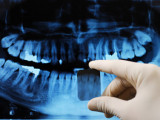

- panoramique ou orthopantomogramme, cette radiographie permet de visualiser la totalité de la bouche, d'une articulation à l'autre.